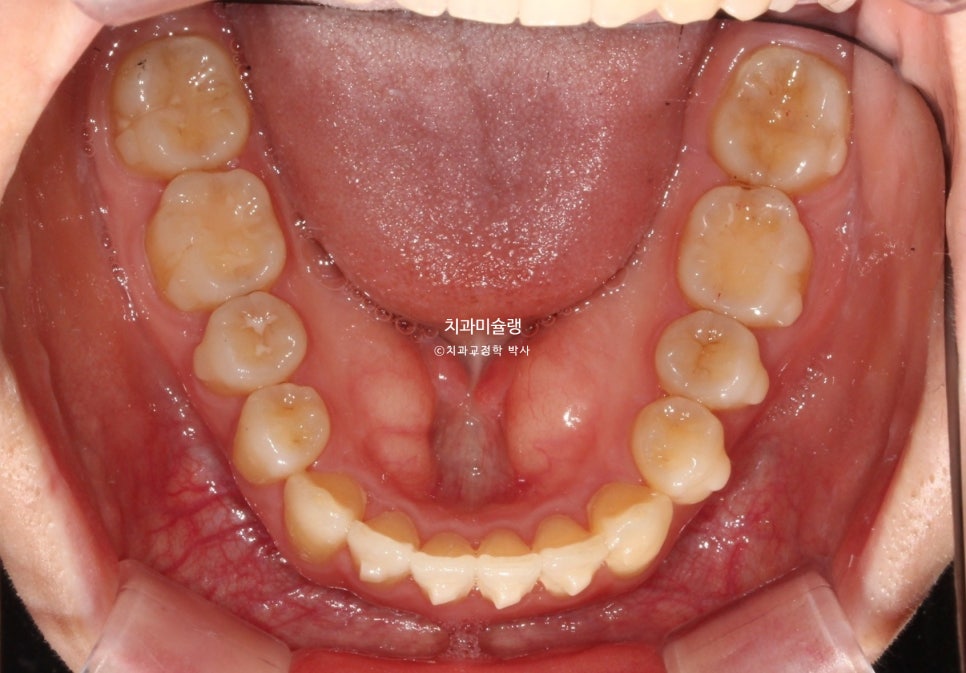

사랑니까지 물샐틈 없는 교합을 보입니다.

교합은 물샐틈 없이 좋으며 사랑니까지 배열되었습니다.